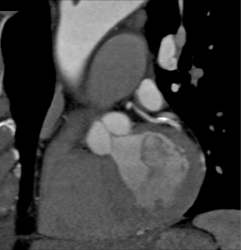

Stent in LAD and Diseased RCA